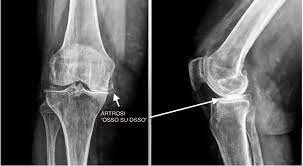

L’artrosi del ginocchio, o gonartrosi, è una malattia cronico-degenerativa che porta ad un danno articolare crescente. Può essere considerata una sorta di “usura” dei capi (superfici) articolari: lo strato di cartilagine che riveste i condili femorali e i piatti tibiali si assottiglia, progressivamente, fino ad esporre l’osso sottostante, che reagisce addensandosi e producendo escrescenze periferiche appuntite, gli osteofiti.